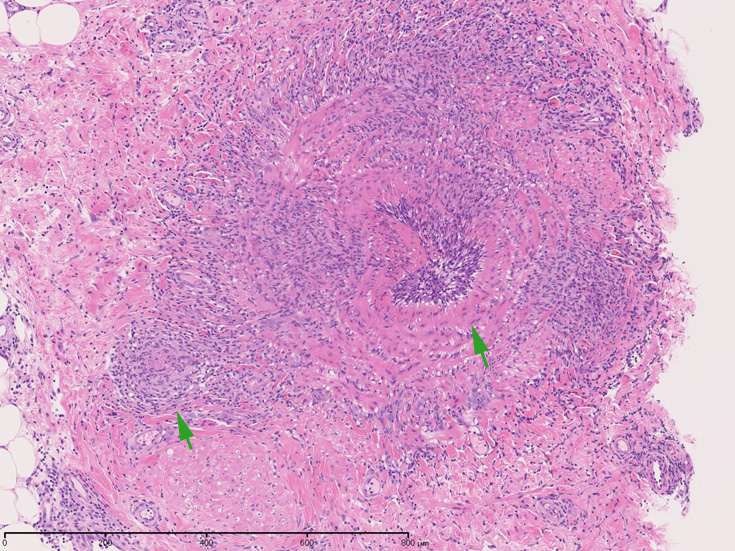

皮膚の血管(静脈・細動脈)病変、脂肪織炎 (サムネイルをクリックすると大きな画像が見られます)

Bec01.jpg

fibrinoidnecrosis01.jpg

vasculitisYa.jpg

fibrinoid necrosis

obstruction.jpg

fibrinoid necrosis(拡大)

Bec05.jpg

免疫染色:血管腔を閉塞する細胞の多くはCD68, CD163陽性細胞. CD34陽性内皮が保たれている。